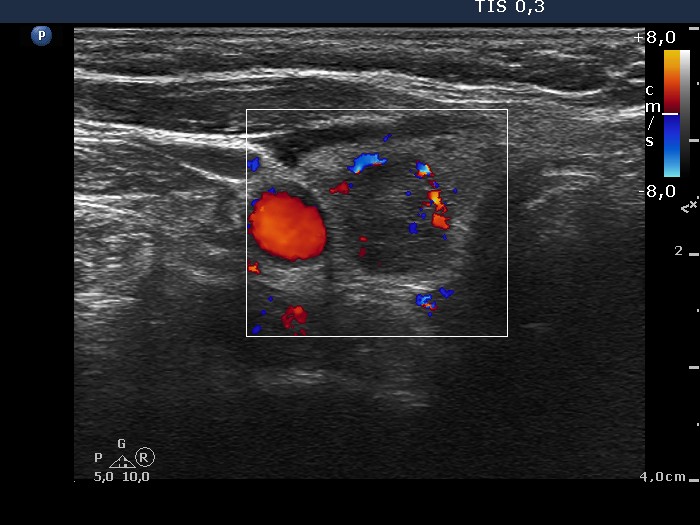

Ultrasonography. The thyroid was echonormal. Beside small hypoechogenic discrete areas there was one hypoechogenic nodule in the right, while two moderately hypoechogenic lesions in the left lobe. The nodule in the upper third of the left lobe was suspicious on ultrasound because of the presence of microcalcifications.

The nodule in the lower pole of the left lobe has lobulated/spiculated margins.

Both the malignant nodule and the oxyphilic adenoma present all three possible signs which might suggest extrathyroidal extension: abutment, bulging and discontinuation of the thyroid capsule. The malignant tumor spread into the capsule but did not break it.